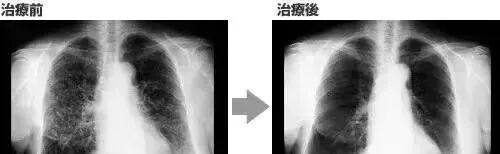

案例3一名广泛期小细胞肺癌患者,在进行4个疗程化疗和4次高度活化NK细胞回输后,患者第一次进行治疗后的CT复查,结果显示,肿瘤缩小到了原来的1/8。而且距发病第六年的CT复查中,仍旧没有发现任何异常及复发的迹象。

△  NK细胞治疗前和治疗期间的CT扫描结果

案例1:国外知名杂志《Oncotargets and Therapy》的一例试验报告显示:NK细胞疗法让晚期肝癌患者肿瘤显著缩小,从生存期仅3个月到超过4年!